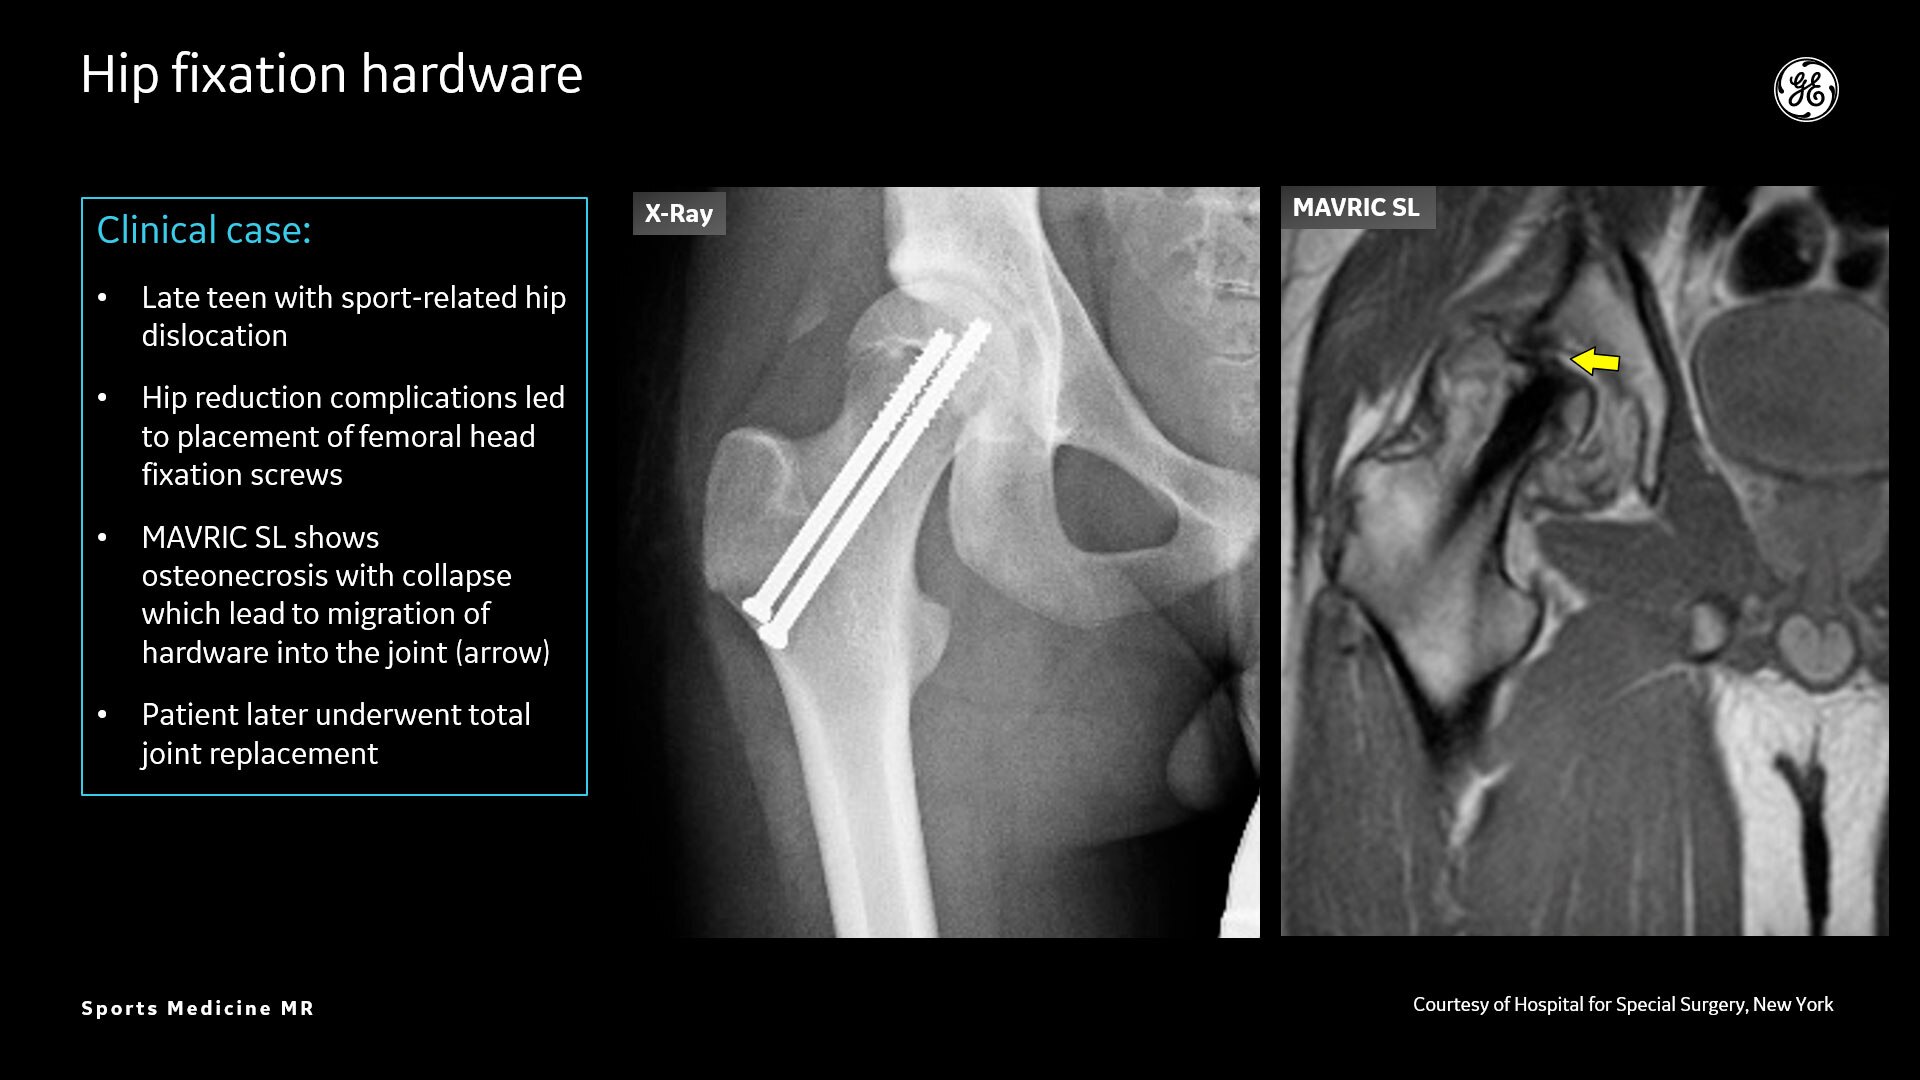

MR lacks ionizing radiation, and is well-suited for longitudinal evaluation of injury in adolescent athletes. The recent introduction of the three dimensional zero-TE (oZTEo) application provides exceptional bone contrast and, like CT, can be reformatted into any arbitrary plane.

AIR™ Recon DL provides high-resolution images with increased SNR at markedly reduced scan times. This technology optimizes the depiction of even small injuries, such as meniscal, labral and ligament tears. The reduction in scan times increases flexibility for individually tailored MR protocols with an additional oZTEo sequence for detailed fracture assessment.